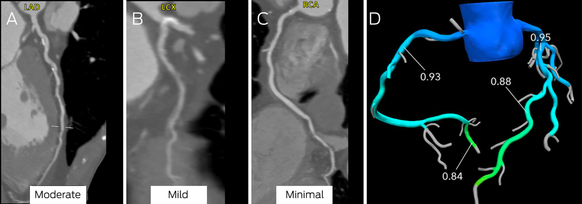

Box 9 – Computed tomography coronary angiography (CTCA) images (A–C) and computed tomography‐derived fractional flow reserve (CT‐FFR) assessment of stenosis (D)*

LAD = left anterior descending artery; LCX = left circumflex; RCA = right coronary artery.

Moderate stenosis is evident in the mid‐left anterior descending coronary artery (A), mild disease in the left circumflex coronary artery (B), and minimal disease in the right coronary artery (C). There was no evidence of ischaemia in the left anterior descending coronary artery (D; CT‐FFR, 0.88; normal > 0.80).